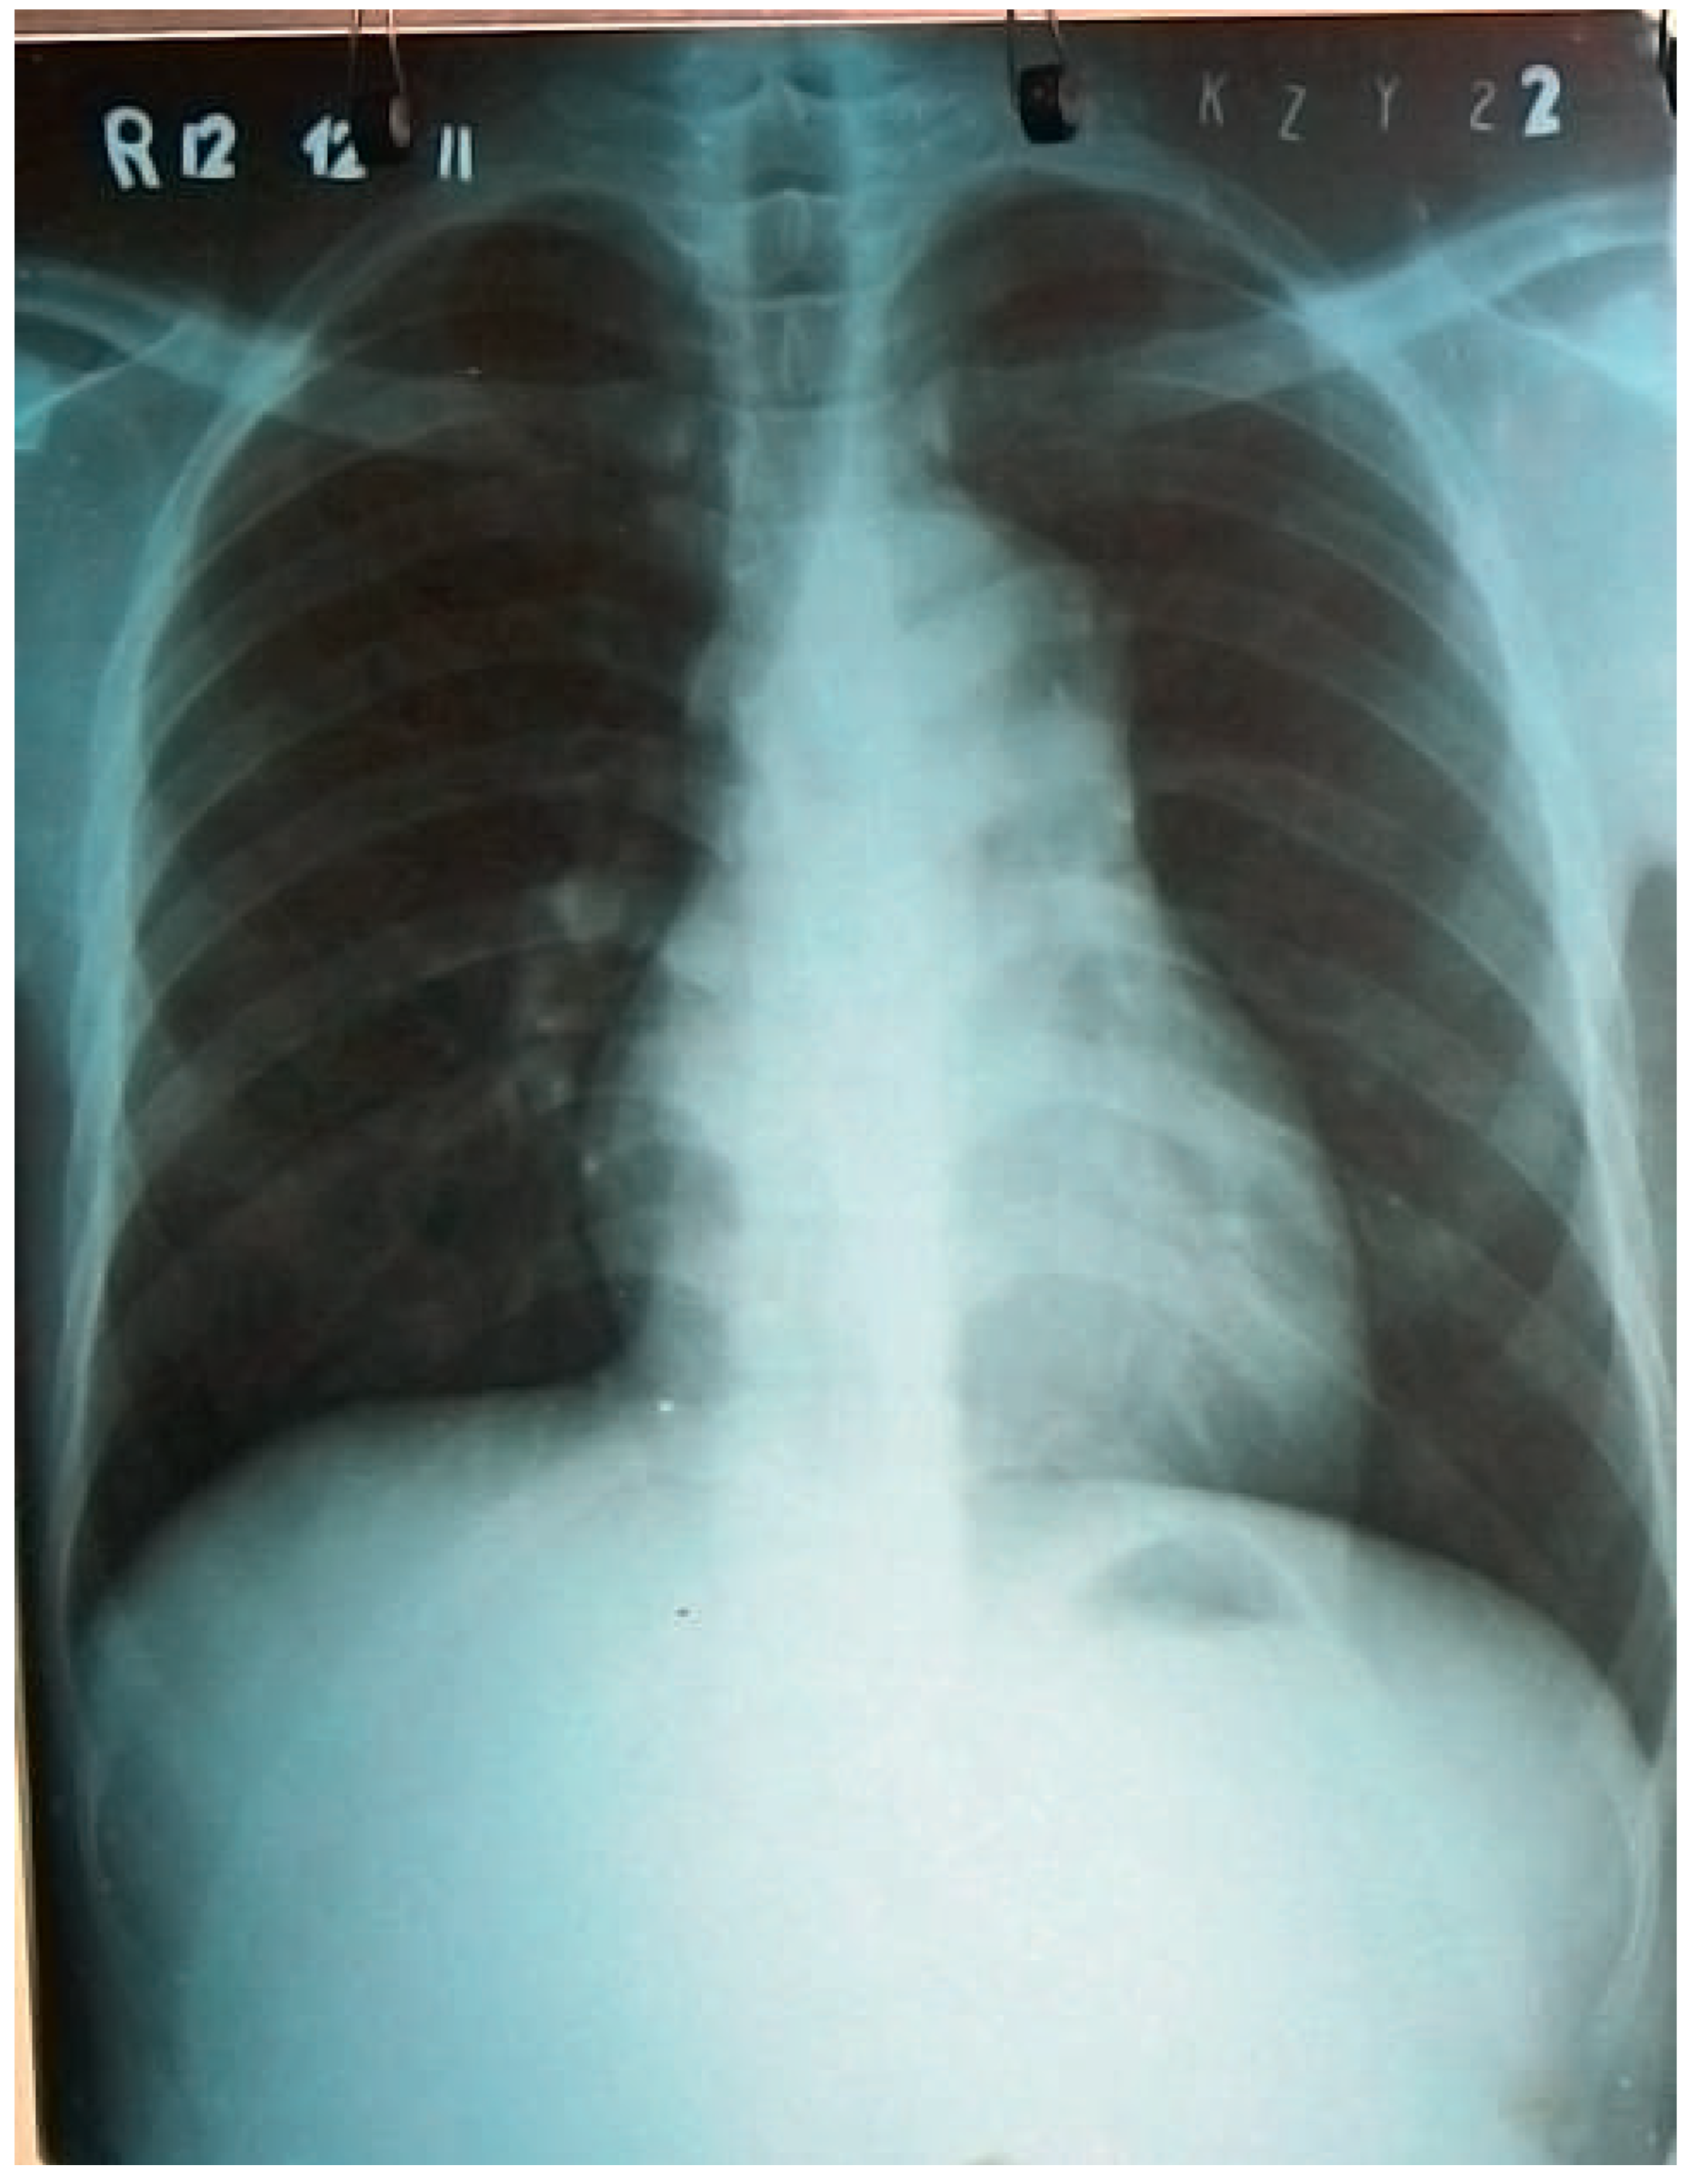

Complete transection of the distal part of the ascending aorta has been found (Figure 5). In addition, the concave part of the proximal aortic arch was ruptured giving a direct view into the proximal descending thoracic aorta. The posterior wall of the false aneurysm was formed by the main pulmonary artery, which crossed the bottom of the aneurysm. Hence, during systole, the main pulmonary artery had obviously been compressed by the pulse-synchronous extension of the thin-walled aneurysm, leading to a functional main pulmonary artery stenosis with resultant right heart failure, right atrial dilatation and serous pericardial effusion.

With a 24 mm vascular prosthesis the distal anastomosis was constructed underneath the aortic arch, its distal end reaching the proximal descending aorta. After completion of the anastomosis, full pump flow was started and the patient rewarmed. Thereafter, the proximal anastomosis of the vascular graft to the ascending aorta was performed, again using strips of autologous pericardium to reinforce it. After complete rewarming, weaning from bypass, decanulation and haemostasis, the size of the right heart chambers had normalised, and the central venous pressure and the shape of the arterial blood pressure curve had become normal (Figure 6). After wound closure, the patient was transferred to the intensive care station. Postoperative recovery was uneventful and the patient was extubated ten hours after surgery. He was discharged home after twelve days in excellent condition.

Figure 5. Complete transection of the middle part of the ascending aorta.

Figure 6. A vascular graft has replaced the ascending aorta; note the marked decrease of right heart chambers after release of the functional pulmonary artery main stem stenosis.